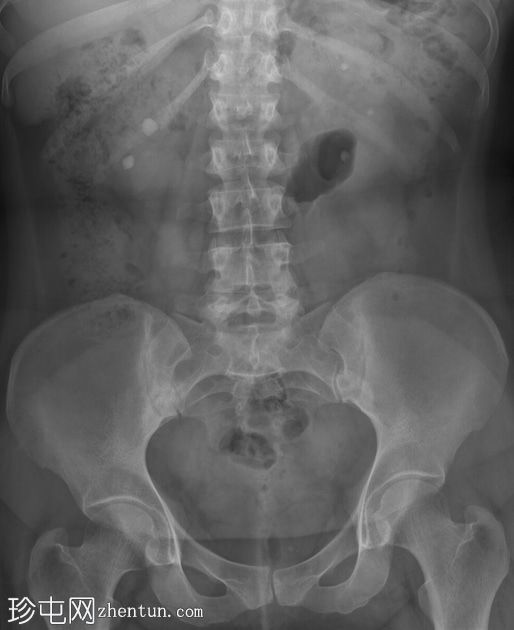

正位片

右肾下盏和中盏可见边界清晰的圆形不透光影,直径分别为10毫米和12毫米。注意左侧上盏、中盏和下盏内各有三个较小的不透光影。

双侧肾结石病例。